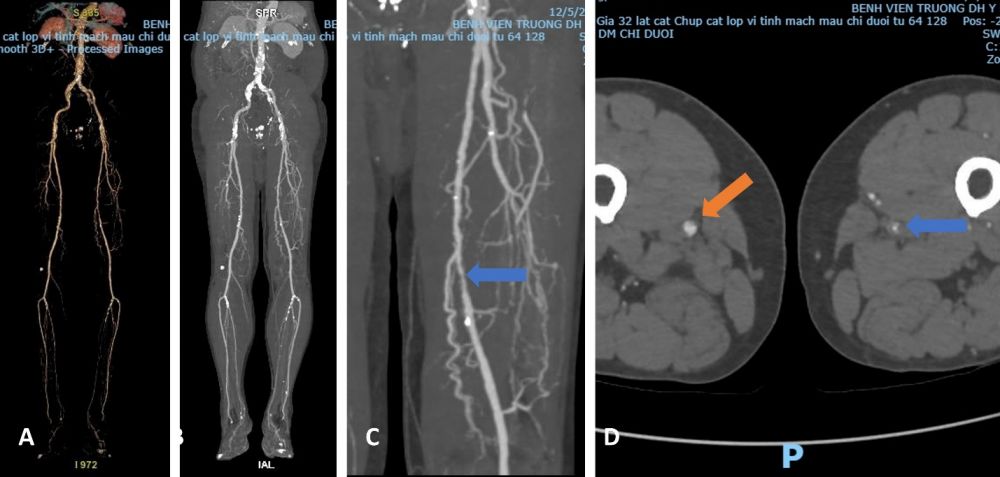

Hinh 2. Hình ảnh cắt lớp vi tính đa dãy đầu thu ở bệnh nhân bệnh lý động mạch ngoại biên. (A) Tái tao 3D toàn bộ hệ động mạch chi dưới hai bên. (B) Tái tạo MIP. (C) Hình ảnh phóng to đoạn động mạch đùi bị hẹp do xơ vữa (mũi tên xanh). (D) Hình ảnh mặt cắt ngang so sánh khẩu kính của động mạch đùi bên phải (mũi tên vàng) và động mạch đùi trái (mũi tên xanh) cho thấy đoạn hẹp khít động mạch đùi trái.